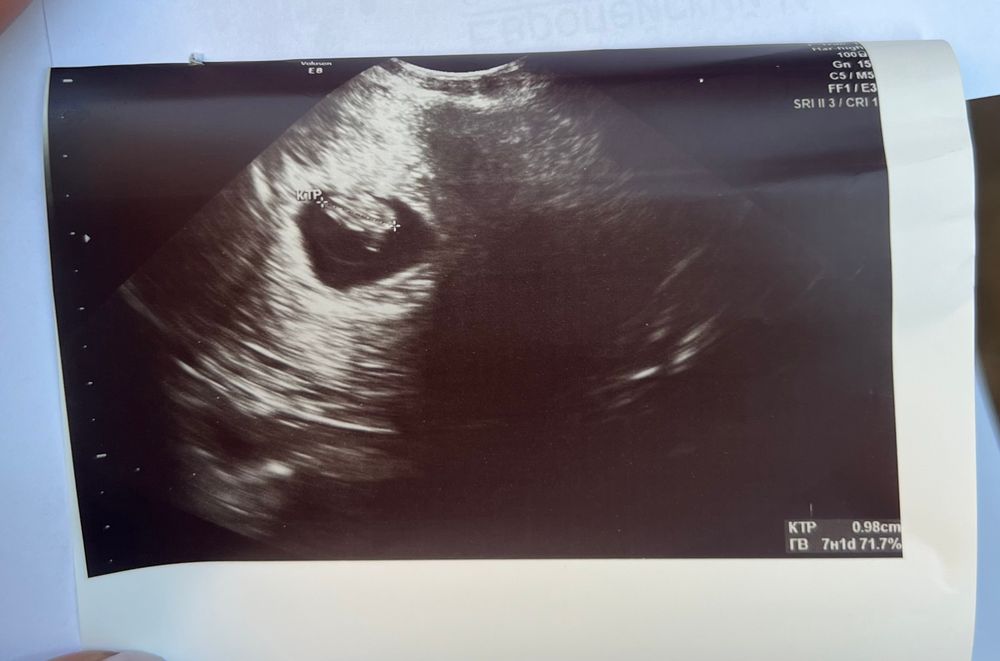

11.07 ПЯ СВД 16 мм, КТР 9,8 мм, СБ 153 в минуту

Получается, ПЯ за 11 дней ничтожно мало выросло. Врач только мельком сказала, что ПЯ маловато, но в целом все в норме, а я и не спросила про разницу, так как делала узи в разных клиниках на разных аппаратах.

На фото узи вроде как не вижу, что эмбриону тесно в ПЯ, вот думаю, может криво померила?

Визуально пя нормального размера по сравнивнению с эмбрионом,думаю ошибка в замерах пя,а вообще разница между пя и ктр для благополучной беременности должна быть не менее 5 мм,у вас даже с этими замерами разница 6 мм,что является нормой,но скорее ошибка и пя больше у вас